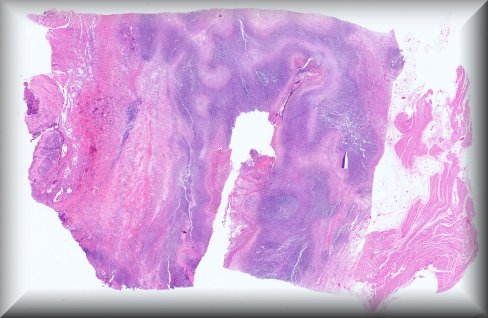

Steffen Heegaard (Copenhagen): Haemolacria in a 72-year-old man. Protocol |